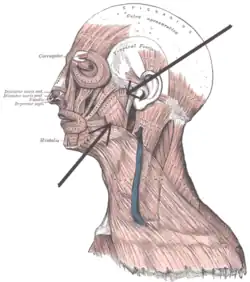

Mięsień żwacz człowieka

Mięsień żwacz (łac. musculus masseter) – w anatomii człowieka parzysty, czworokątny, gruby i krótki mięsień żucia, znajdujący się na bocznej powierzchni gałęzi żuchwy[1]. Składa się z dwóch warstw – powierzchownej (pars superficialis, z włóknami biegnącymi ukośnie) i głębokiej (pars profunda, z włóknami biegnącymi pionowo)[1]. Przyczep początkowy warstwy powierzchownej to dolny brzeg kości jarzmowej, zaś warstwy głębokiej to głównie łuk jarzmowy, jednak część włókien przechodzi pod łukiem do dołu skroniowego oraz torebki stawowej i krążka stawowego stawu skroniowo-żuchwowego. Przyczep końcowy obu warstw to powierzchnia zewnętrzna kąta żuchwy, tzw. guzowatość żwaczowa; niektóre włókna biegną dookoła kąta żuchwy i łączą się z włóknami mięśnia skrzydłowego przyśrodkowego.

Skurcze żwacza unoszą żuchwę (przy otwartych ustach) i przyciskają do siebie zęby szczęki i żuchwy, umożliwiając tym samym gryzienie i przeżuwanie pokarmu. Część włókien współdziała ponadto przy wysuwaniu żuchwy (warstwa powierzchowna – włókna biegnące skośnie).

Unerwienie stanowi nerw żwaczowy – gałązka nerwu żuchwowego (V3, trzeciej gałęzi nerwu trójdzielnego)[1].